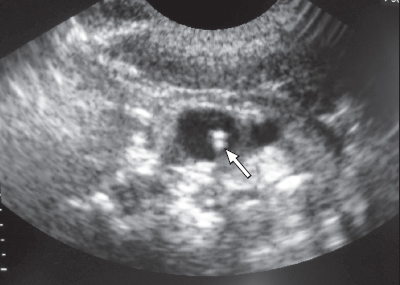

Яремная вена на узи

Яремная вена на узи 111 фотографий